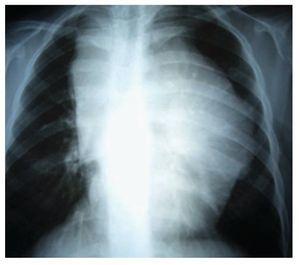

Adolescente femenino de 12 años de edad con antecedentes de cáncer materno en cinco miembros de la familia, con un cuadro de seis meses de evolución con deterioro de su estado general (astenia, adinamia, hiporexia, fiebre vespertina hasta de 380, pérdida de 8 kg de peso) y adenopatías periféricas. En la exploración física se percibe conglomerado ganglionar supraclavicular derecho e izquierdo de 5 cm por 3 cm, red venosa colateral en la cara antero-superior de hemitórax izquierdo, hipoventilación superior izquierda con matidez a la percusión; el resto de la exploración resulta negativa. Los exámenes de laboratorio fueron normales, excepto la velocidad de sedimentación globular 30 mm/60 min. La radiografía de tórax mostró una gran masa en el mediastino (Imagen 1); la tomografía axial computarizada de tórax reveló una imagen lobulada, hiperdensa hacia el parénquima pulmonar, localizada en el mediastino medio, anterior y superior, que desplazaba la silueta cardiaca hacia abajo y hacia el lado izquierdo, la cual mostraba reforzamiento leve cuando se aplicó contraste. Además, comprimía, en su porción posterior, ambos hilios sin obliterarlos; el parénquima pulmonar sin alteraciones (Imagen 2).

Imagen 1. Radiografía simple de tórax, donde se observa una gran masa mediastinal.